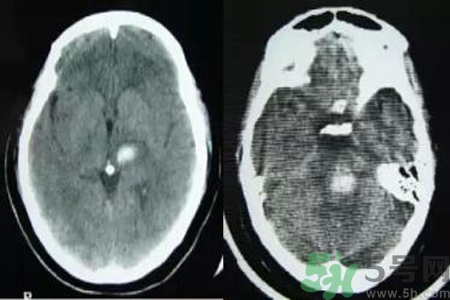

腦出血也稱腦溢血。顧名思義,腦出血是指腦實(shí)質(zhì)內(nèi)的血管破裂,血液溢出即為腦出血。那么腦出血的發(fā)病因素是什么?腦出血的并發(fā)癥有哪些?

引起腦出血的病因很多,最常見的病因是高血壓動(dòng)脈粥樣硬化,其次為先天性腦血管畸形或動(dòng)脈瘤、血液病、腦外傷、抗凝或溶血栓治療、淀粉樣血管病等引起的腦出血。根據(jù)病因分類如下。